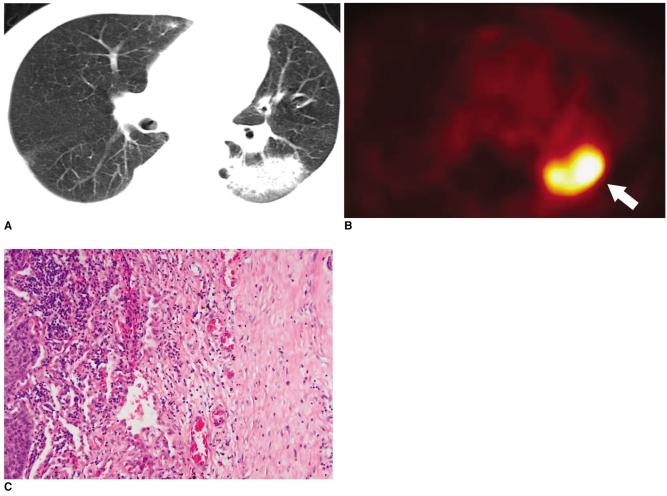

Fluorodeoxyglucose (FDG)-positron emission tomography (PET) is being used more and more to differentiate benign from malignant focal lesions and it has been shown to be more efficacious than conventional chest computed tomography (CT). However, FDG is not a cancer-specific agent, and false positive findings in benign diseases have been reported. Infectious diseases (mycobacterial, fungal, bacterial infection), sarcoidosis, radiation pneumonitis and post-operative surgical conditions have shown intense uptake on PET scan. On the other hand, tumors with low glycolytic activity such as adenomas, bronchioloalveolar carcinomas, carcinoid tumors, low grade lymphomas and small sized tumors have revealed false negative findings on PET scan. Furthermore, in diseases located near the physiologic uptake sites (heart, bladder, kidney, and liver), FDG-PET should be complemented with other imaging modalities to confirm results and to minimize false negative findings. Familiarity with these false positive and negative findings will help radiologists interpret PET scans more accurately and also will help to determine the significance of the findings. In this review, we illustrate false positive and negative findings of PET scan in a variety of diseases.